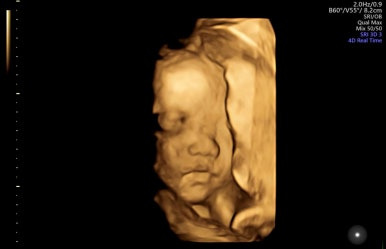

28주 1일

입체초음파로 태아의 얼굴을 볼 수 있는 시기이다!

제일 기다렸던 때이고, 다행히 태아 얼굴을 볼 수 있었다.